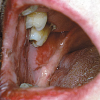

Äge leukeemia: Haigus algab palaviku halva enesetunde, tonsilliidi, suu limaskesta haavandumisega: Hüperplastiline gingiviit Veritsus Petehhiad Haavandid Infektsioonid Gingiva on sageli suus esimeseks kahjustuspiirkonnaks. Igemetel on...